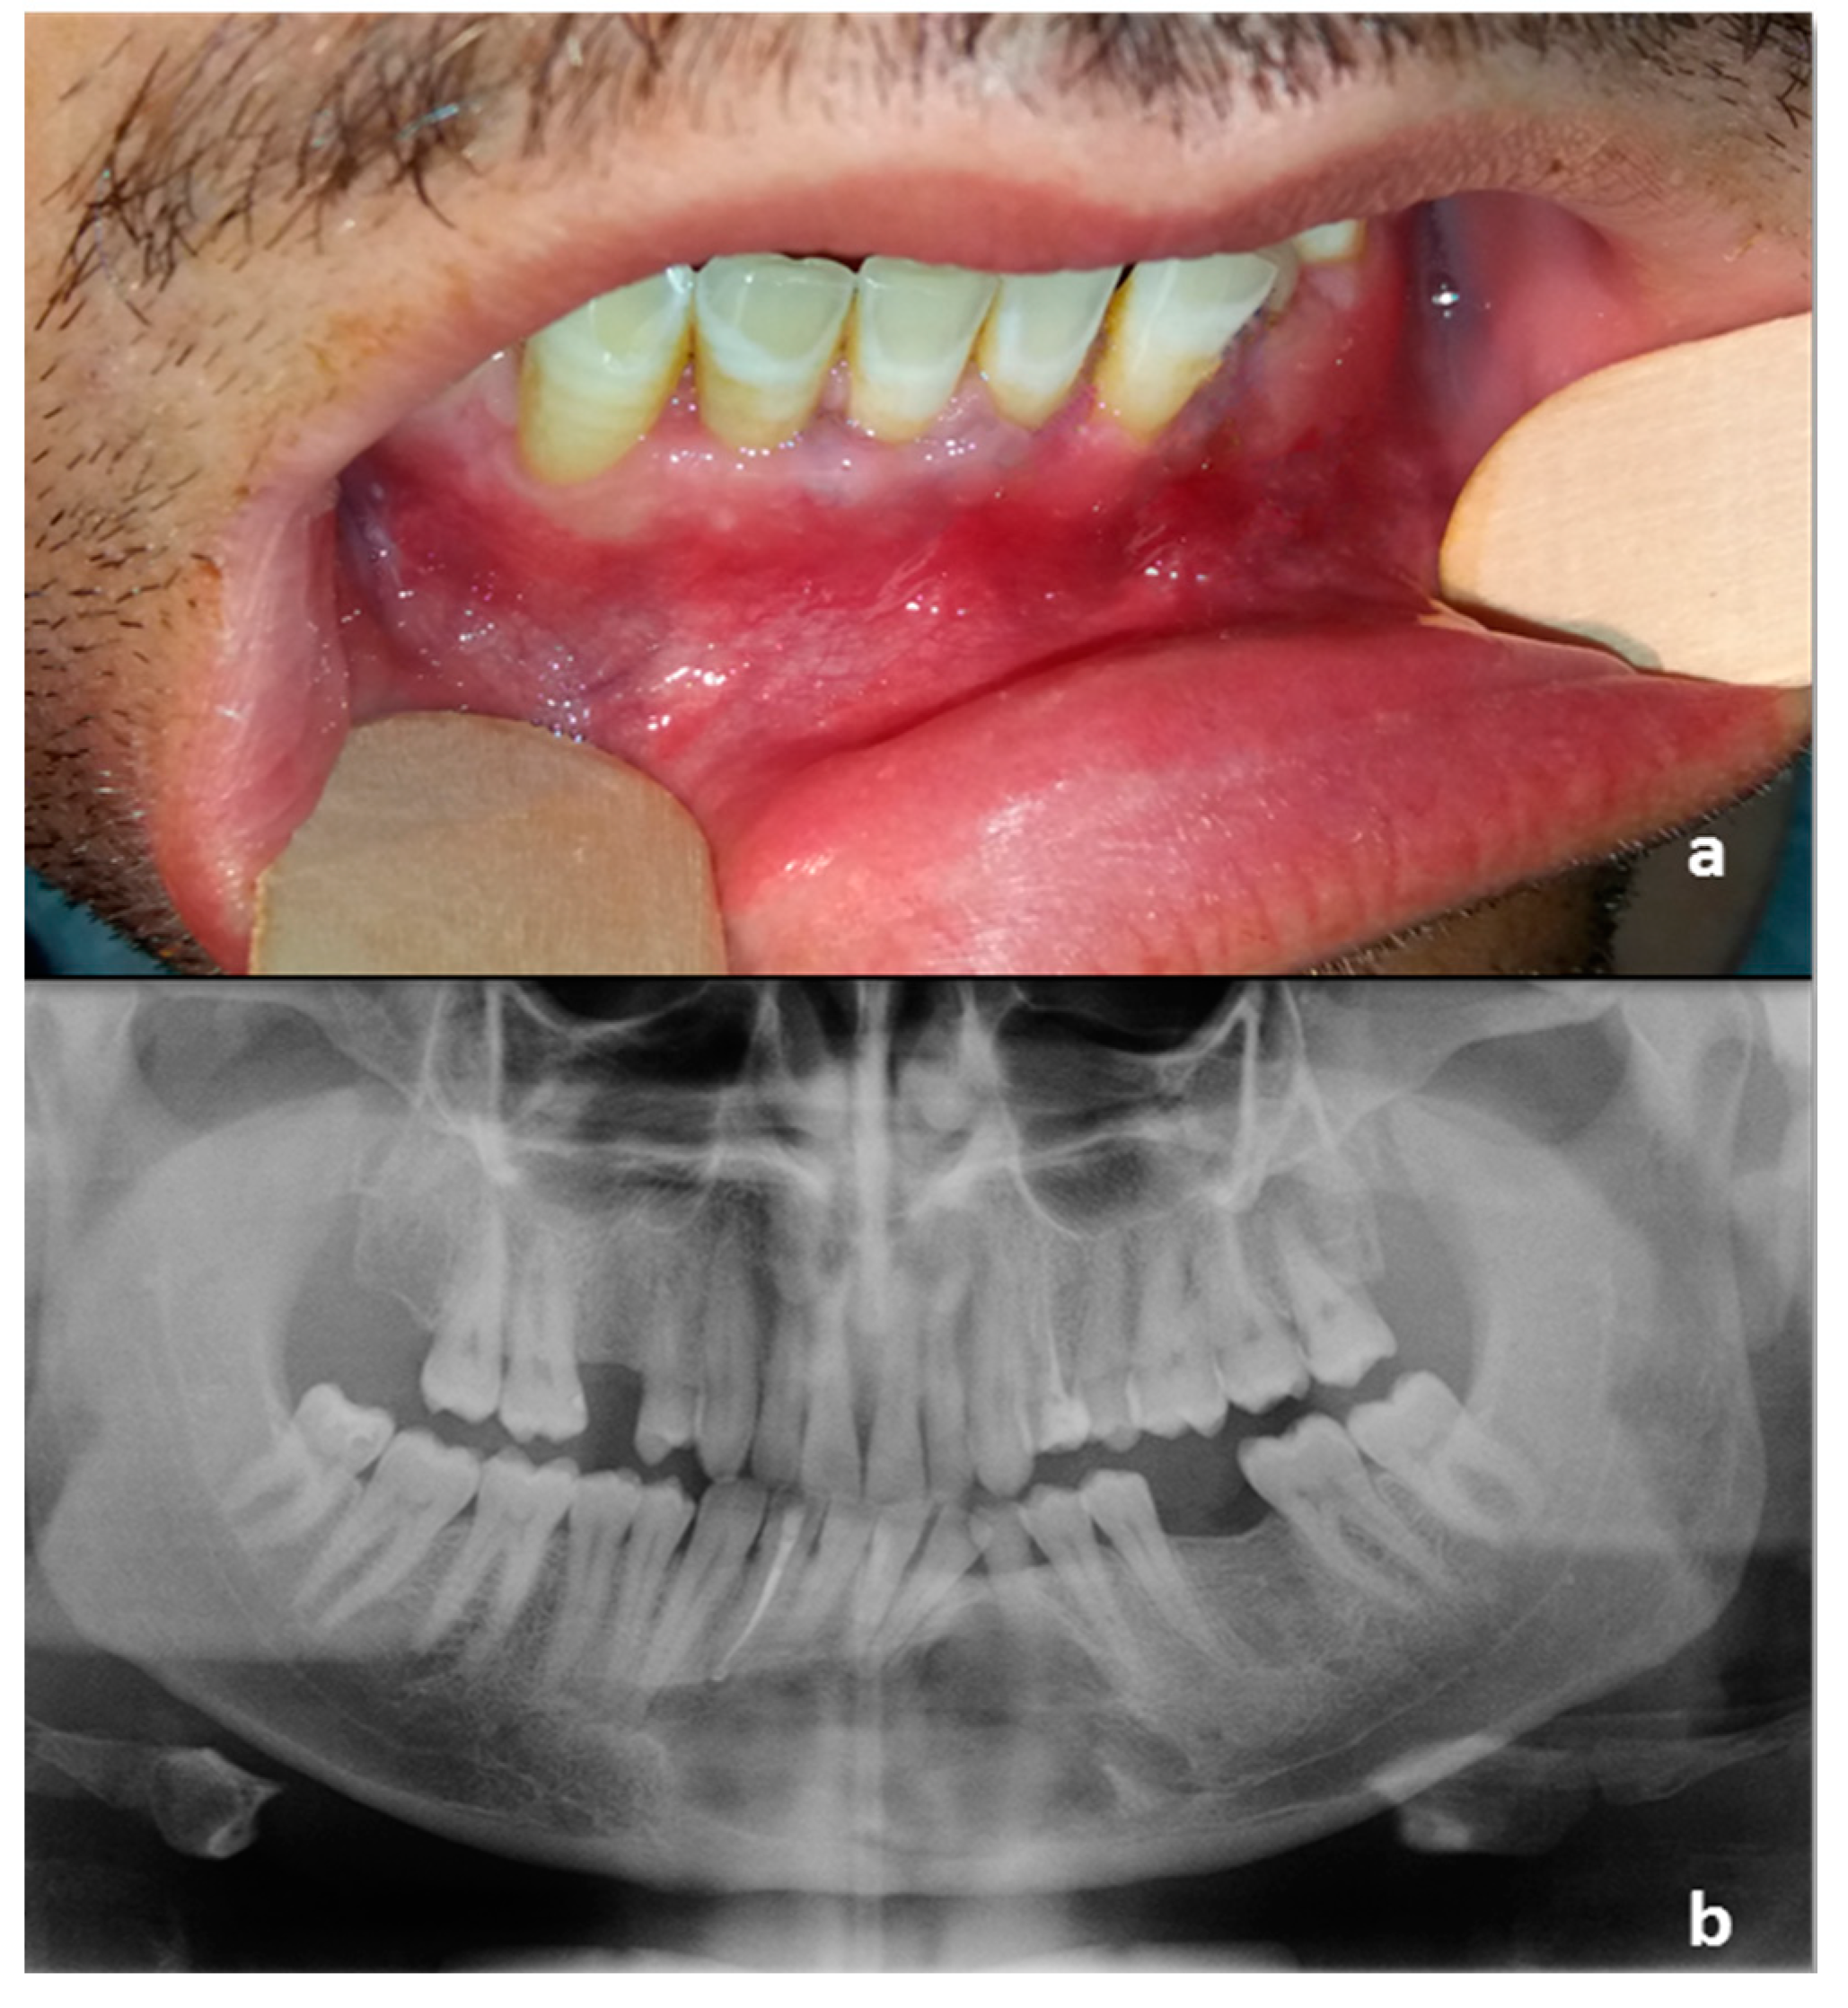

A 34-year old male presented to a private dental outpatient clinic with pus drainage and swelling in the III quadrant of the oral cavity, suggesting a dental infection. Collecting the medical history, the patient referred that 10 years before in an orthopantomography (OPG), an incidental finding of a radiotransparent lesion was documented (Figure 1). The mandible radiolucency was related to an impacted 33 dental element (left lower canine), a fact that had been compatible with the diagnosis of a dentigerous cyst (Figure 1). The patient was aware of the presence of this cystic lesion, but he had refused to remove it despite the dentist’s advice. For purulent discharge, the patient was treated with an antibiotic therapy (ceftriaxone 1g IM, 1 infiltration/day, for 1 week) prescribed by the private dentist. A cone-beam computed tomography (CBCT) of the mandible was also performed; no atypical radiologic signs were revealed (Figure 2). Nevertheless, a second episode of infection developed two months later, and it was treated again with antibiotic therapy prescribed by the private dentist (3 cycles of amoxicillin/clavulanate 1g per os) followed by ceftriaxone (1g IM, 1 infiltration/day, for 1 week) that we prescribed after our consultation for poor clinical response to previous treatment. The following month the patient had a new infective episode and was hospitalized in our department for further diagnostic investigations.

Figure 1.

During a routine orthopantomography (2007) performed 10 years before PIOSCC diagnosis, an impacted left lower canine, and a related incidental radiolucent cystic lesion was detected, compatible with the diagnosis of a dentigerous cyst.

Figure 2.

Cone-beam computed tomography (CBCT) of the mandible performed in January 2017 after the first infective episode and showing no atypical radiologic findings. The osteolytic alveolar defect (white arrow) has led to the recurrent oral discharge.

(a) Intraoral preoperative picture. The fistula was not noticeable after antibiotic therapy. No ulceration of the oral mucosa was detectable; (b) Orthopantomography following the diagnostic biopsy and lower canine extraction.

In our case, orthopantomography (Figure 1) and CT (Figure 2) showed a uniloculated 38 × 14 mm osteolytic area affecting the chin symphysis and extending in the left paramedian region. The lesion interrupted the vestibular bone cortex but spared the lingual one.